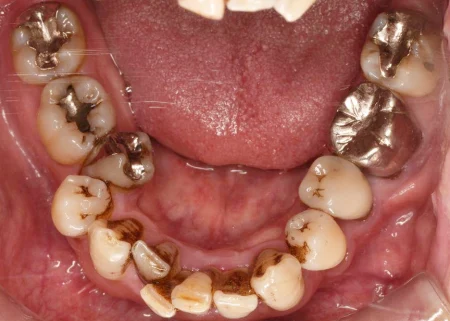

治療前

| カウンセリング・診断結果 | 拝見すると、お口全体の歯の表面に重度の着色が見られました。 患者様は「日ごろからよくコーヒーを飲む」とのことで、これが着色の原因と考えられました。 さらに、レントゲン写真や歯周検査の結果から、歯肉に炎症が起こり歯を支える骨が次第に溶けていく「歯周病」の進行も認められました。 |

| 行ったご提案・治療内容 | 歯周病を放置したまま詰め物をやり直すと、歯と詰め物の間に隙間が生じやすく、その隙間から虫歯になったり歯周病がさらに悪化したりする場合があります。 また、着色があると歯の表面のざらつきが原因で、食べ物の残りカスに細菌が繁殖した「プラーク」が付着しやすくなります。 そのため、詰め物をやり直す前に歯周病の治療と着色除去を行い、歯と歯肉の状態を改善する必要があることを丁寧にご説明し、ご理解とご了承を得ました。 歯周病治療は、歯肉の上や歯肉の中にあった硬い細菌の塊「歯石」を除去しました。 また、専用機械による歯の表面のブラッシングや、ジェット水流と専用パウダーで汚れを除去する「エアフロー」で着色を取り除きました。 着色の度合いが強かったため、歯周病治療と着色除去を並行して4回に分けて実施しました。 |